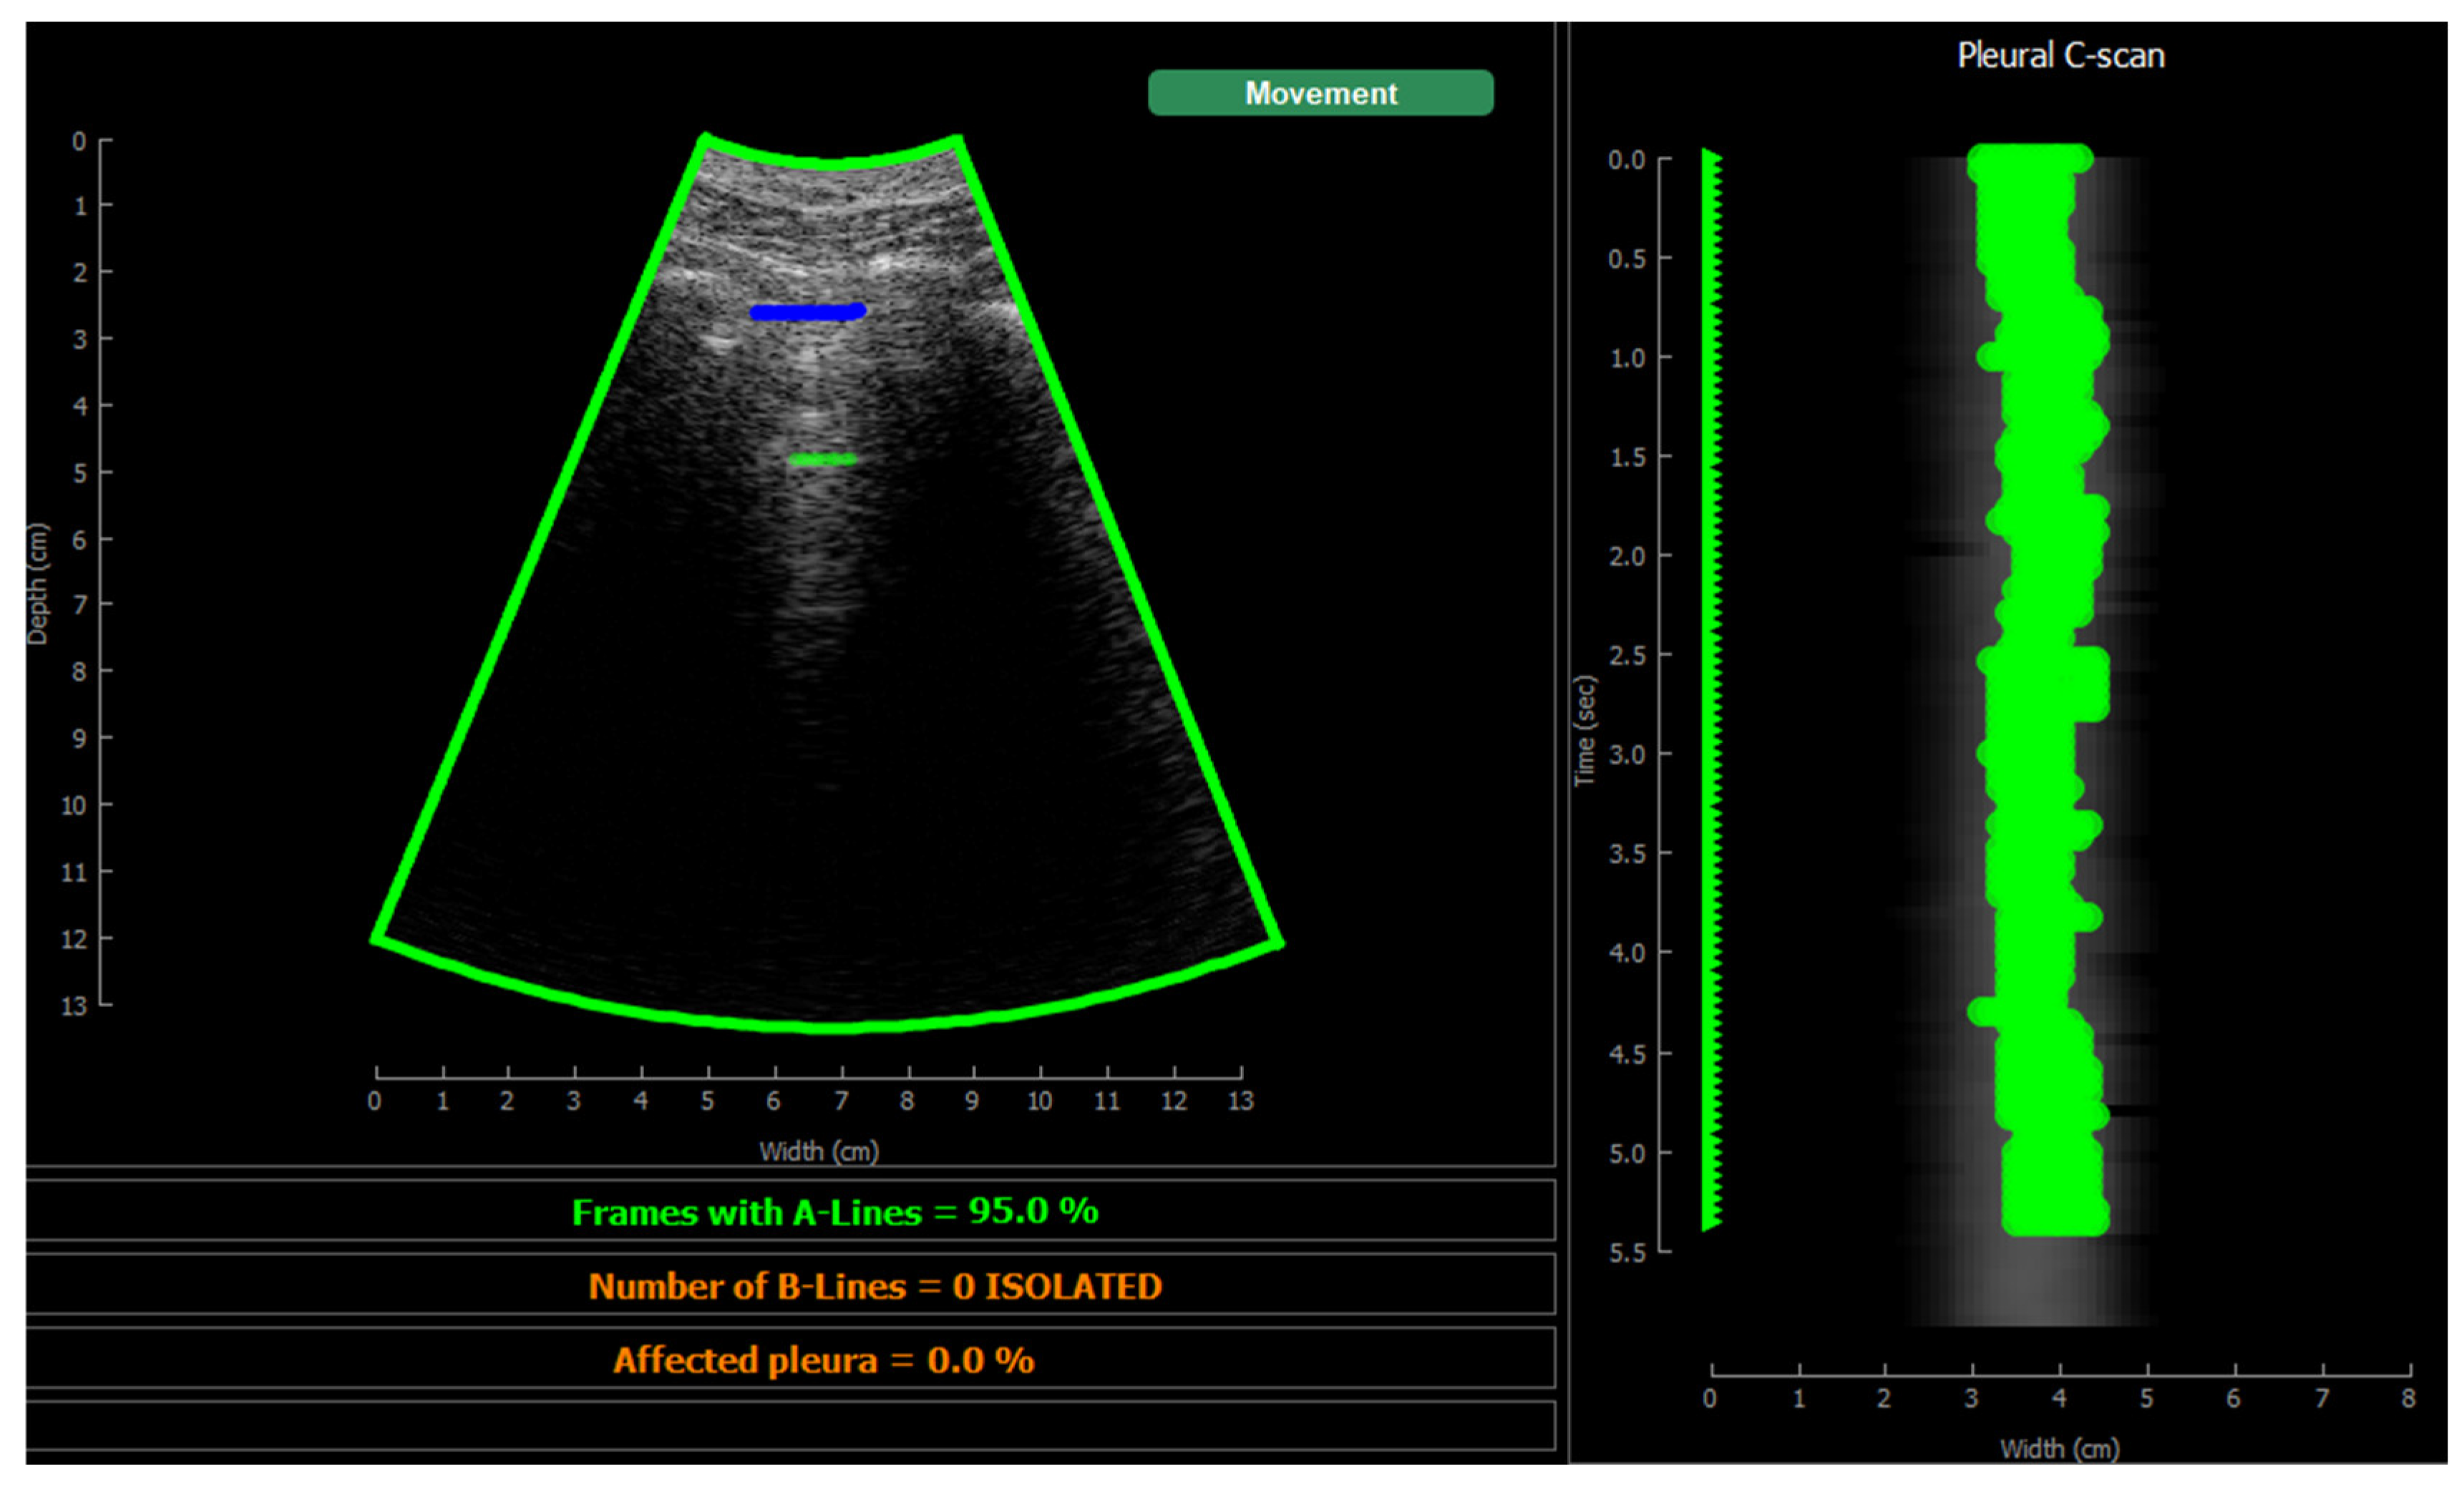

Figure 10 shows the screen shown to the user. On the left, the acquired sector-scan images are shown in real-time, with several overlays coming from the processing algorithm. When the image is valid for being evaluated, the contour of the image turns green, and so the label “movement” on the upper right corner. If the image fails to pass any of this criterion, the contour line turns red, and so the labels that triggered the event. Therefore, the physician can freely move the probe on the patient chest until theses indications turn green, and then hold probe steady to acquire a video of 3 seconds that will be saved for each of the 12 regions to be examined according to the protocol.

This image also overlays, in real-time, the findings of the neural network. The pleura is marked with blue points, A-Lines with green points, B-Lines with orange points and consolidations with red points. Furthermore, a series of statistics and messages are shown in the lower part of this image: The percentage of frames with A-Lines in the last 6 seconds, the number of isolated B-Lines, calculated as the sub-regions with an average 6dB drop in the angular direction within the region where B-Lines were detected, the percentage of the affected pleura calculated as the number of scan lines affected by B-Lines over the total number of scan lines where the pleura was detected, and a label in red indicating that a consolidation when present.

Figure 13. Application visualization sample: a)B-lines (orange) and consolidation (red) detection; b)normal lung with A-lines(green); c) probe movement detected; d) B line (orange) and A-line (green) deteccion on a Lung phantom. On the right of each image the C-scan image is shown.